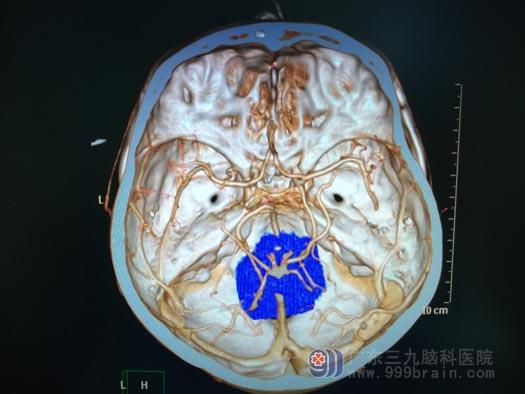

▲术前CTA

肿瘤来源于四脑室底,与脑干关系密切。第四脑室是一个非常重要的解剖区域,腹侧毗邻桥脑、延髓等脑干结构,又是脑室系统内脑脊液循环通路的最后环节,由于瘤体周围有重要的神经、血管组织,故手术对肿瘤进行彻底切除难度较大。目前情况下,手术仍是首选的治疗方法。